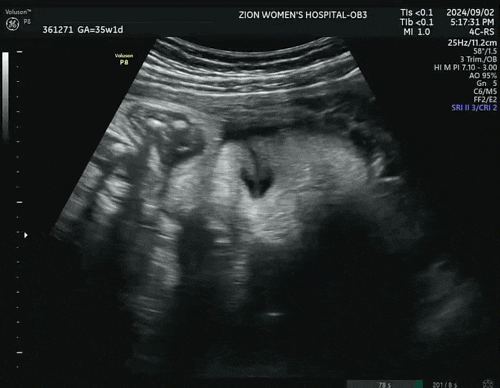

Ep16. 37주차 기록 | 추석, 심심한 출산휴가, 아기크기 2.8kg, 태아 딸국질, 산전마사지

추석겸 출산휴가가 시작된 37주! 지금 생각하면 일 더할걸싶다. 이렇게 늦게 나올 줄 누가 알았겠는가 ㅎㅎ...

Ep14. 35주차 기록 | 시온여성병원 막달검사, 35주 아기크기, 정부지원 수원시 산후도우미 신청

진짜 마지막을 향해 달려가는 임신기록 35주차 정기검진 진료비 193,320원 / 이제 바우처 없음 1. 출산 안...